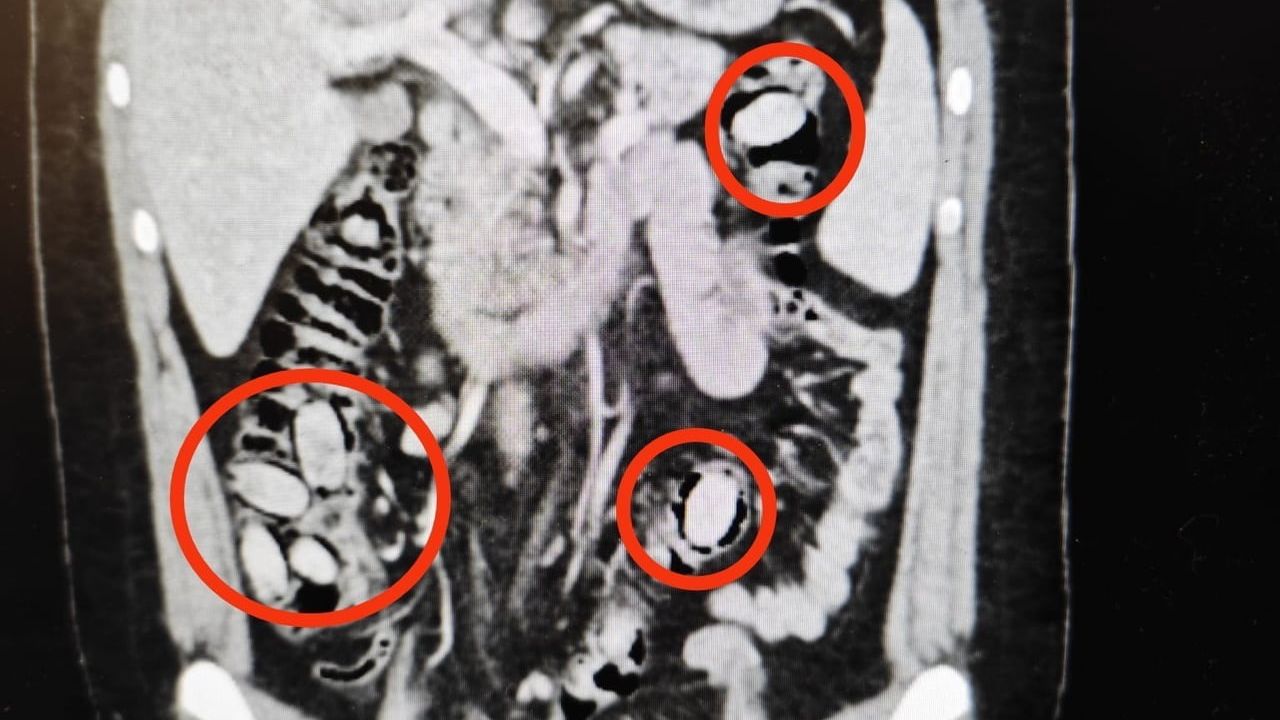

Hastanede yapılan detaylı tetkikler sonucunda şahsın yutmak suretiyle midesinde 44 kapsül metamfetamin taşıdığı belirlendi. Sağlık ekiplerinin gerçekleştirdiği cerrahi müdahale ile kapsüller şahsın bedeninden çıkarıldı.